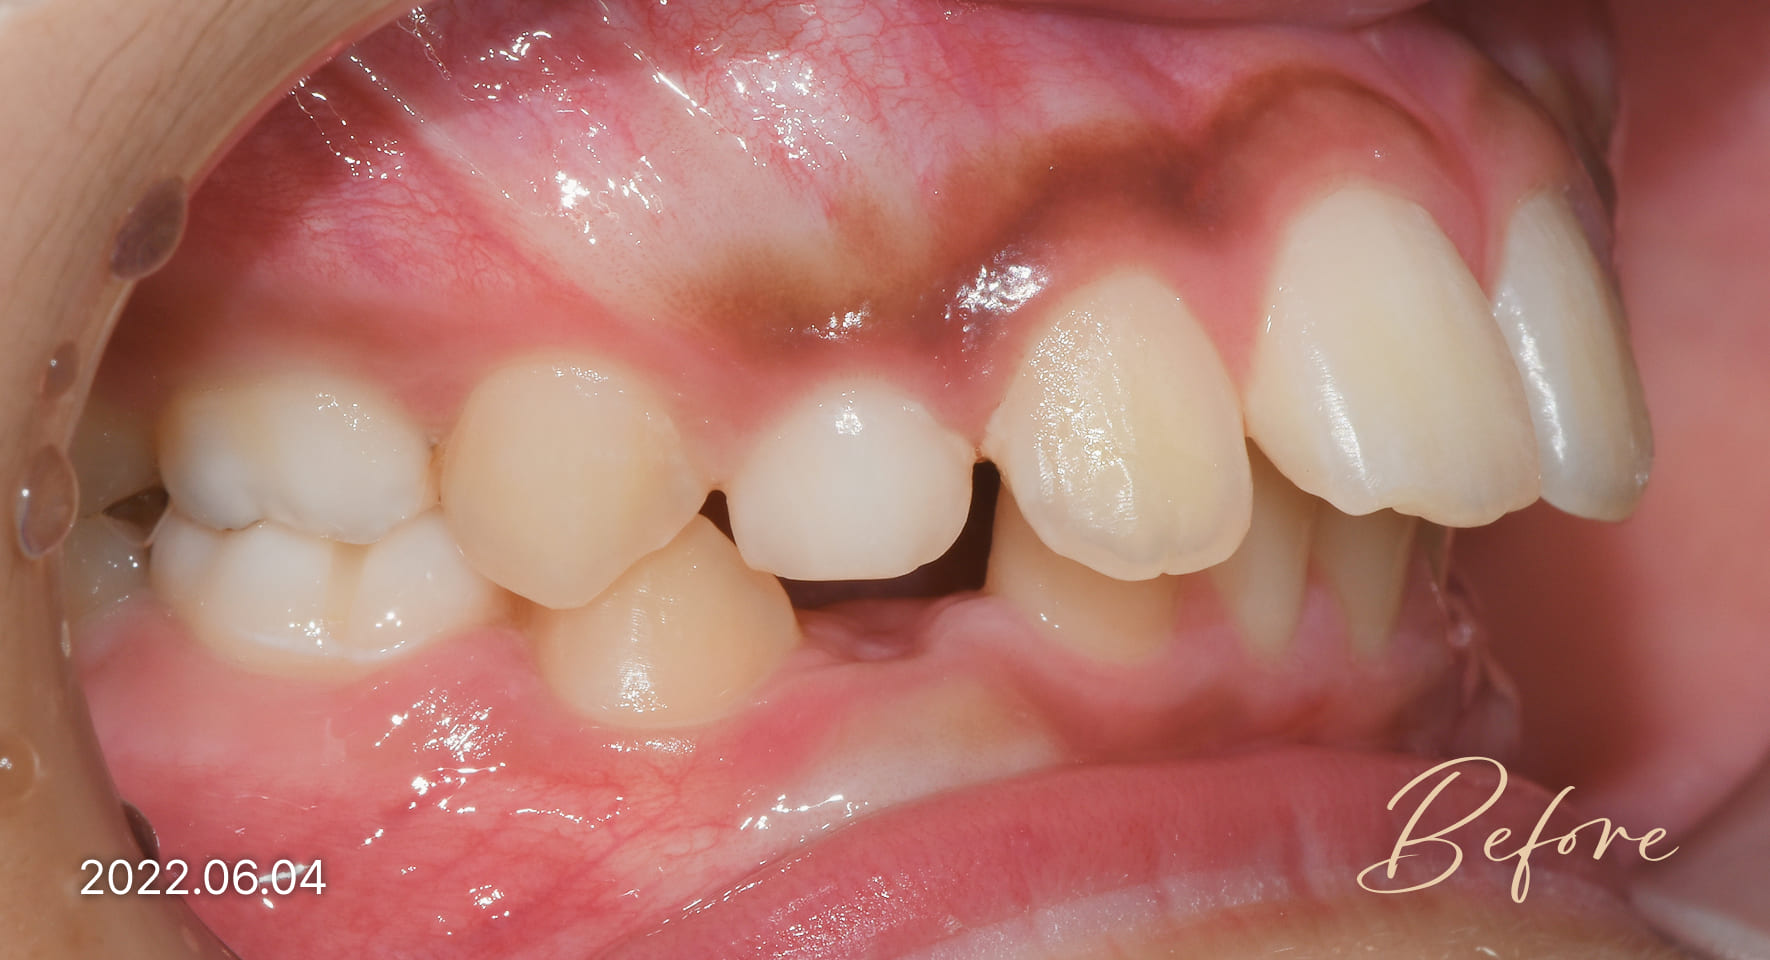

성장기 교정 치료사례

본 사진은 진심을담은치과교정과 치과의원에서

치료한 환자의 동일 인물 전·후 사진입니다.

개인의 구강 상태 및 관리 방법에 따라 통증 및 잇몸 염증,

턱관절 불편감 등의 부작용이 발생할 수 있습니다.

치료 전 치료 후